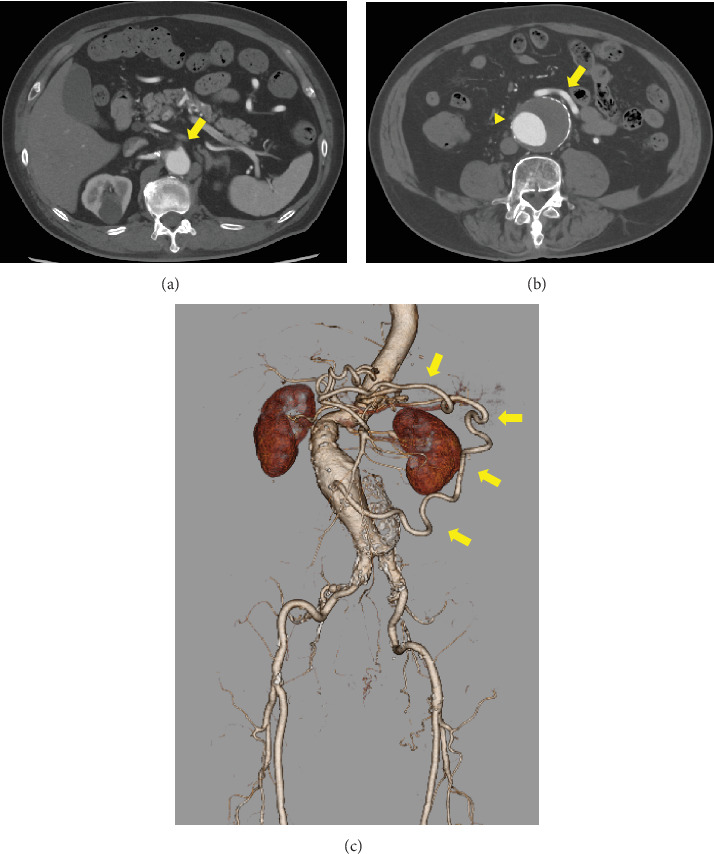

一名78岁男性被诊断为腹主动脉瘤伴肠系膜动脉弯曲。术中应用肠系膜下动脉灌注进行腹主动脉置换和肠系膜下动脉重建。将4-Fr动脉鞘插入左肱动脉,将10-Fr球囊导管插入肠系膜下动脉灌注。术中肠血流良好,患者术后病程良好。这种方法对于肠系膜动脉曲流患者的腹主动脉手术是一种简单有效的选择。

A 78-year-old man was diagnosed with an abdominal aortic aneurysm with a meandering mesenteric artery. We performed abdominal aortic replacement and inferior mesenteric artery reconstruction using intraoperative inferior mesenteric artery perfusion during surgery. A 4-Fr arterial sheath was inserted into the left brachial artery, and a 10-Fr balloon catheter was inserted into the inferior mesenteric artery for perfusion. The intraoperative intestinal blood flow was satisfactory, and the patient's postoperative course was favorable. This method was an easy and effective option for abdominal aortic surgery in patients with a meandering mesenteric artery.